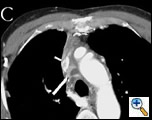

The patient was taken to the operating room and sternotomy performed after division of several large collateral chest wall veins. The pericardium was opened and resection of all thymic tissue was undertaken starting at the diaphragm (Figure 3). The SVC was transected at the confluence of the right subclavian and jugular veins and found to be filled with fibrotic tissue (Figure 4A). Frozen section examination of the luminal contents identified benign fibrotic tissue. The SVC was mobilized to the level of the right atrium en-bloc with the tumor, the azygos vein was divided, and a wedge resection of the medial aspect of the right upper lobe was performed. At this point, the tumor had been completely mobilized except for an intravascular extension through the SVC into the right atrium (Figure 4B).

The patient was placed on cardiopulmonary bypass via the aorta and inferior vena cava. The SVC was resected with the atrium and the tumor removed en-bloc (Figures 5-7). The atrium was closed and the patient weaned off cardiopulmonary bypass. The patient was extubated on postoperative day 2 and discharged home on postoperative day 7. Final pathology revealed a malignant thymoma with vascular and lung invasion.